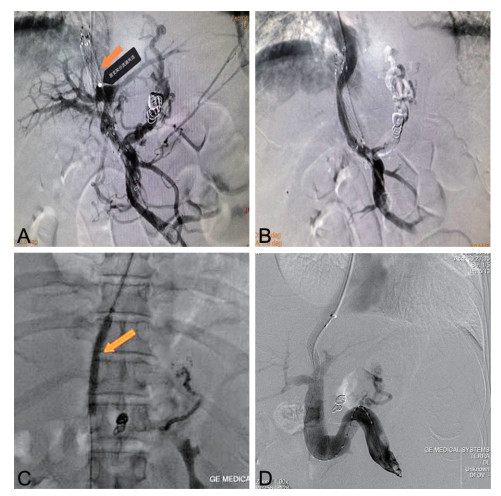

Construction and verification of prediction model and treatment strategy for shunt loss after portal hypertension TIPS

QIAN Jinyu, YANG Peipei, ZHANG Yang, XIE Bo, WU Di, TANG Xiaoyun, ZHANG Leiming, TAN Yulin, ZHANG Zichen

2025, 23(7): 1107-1110. doi: 10.16766/j.cnki.issn.1674-4152.004075

429 3

Abstract:

Objective   To identify the risk factors of shunt dysfunction after transjugular intrahepatic portosystemic shunt (TIPS) in patients with portal hypertension, to construct and verify the clinical prediction model, and to formulate corresponding countermeasures for different types of shunt dysfunction, so as to provide reasonable treatment for patients.   Methods   The clinical data of 120 patients who underwent TIPS in the interventional department of the First Affiliated Hospital of Bengbu Medical University from January 2020 to December 2024 were retrospectively analyzed. Subsequent to the surgical procedure, the subjects were categorized into two distinct groups, namely the shunt dysfunction group and the non-dysfunction group, with the respective numbers amounting to 35 and 85 cases. Variables with significant differences were included in multivariate logistic regression analysis to determine the independent risk factors, and a prediction model was constructed based on this. The discrimination capacity of the model was evaluated by means of the ROC curve. Finally, the corresponding countermeasures are proposed for the various types of shunt failure.   Results   Multivariate logistic regression analysis demonstrated that anticoagulation therapy (OR=15.754, P=0.030), portal vein thrombosis (OR=0.052, P=0.008) and portal vein puncture site (OR=0.064, P=0.007) were independent influencing factors for shunt dysfunction after TIPS. The area under the ROC curve (95% CI) of the constructed model was 0.933 (0.882-0.983), and the corresponding optimal cut-off value was 0.866. The sensitivity was 0.894, and the specificity was 0.971.   Conclusion   Therapy, portal vein thrombosis and portal vein puncture site are independent influencing factors of shunt dysfunction after TIPS. The prediction model constructed accordingly has the potential to assist clinicians in the early identification of risks and the implementation of intervention measures.